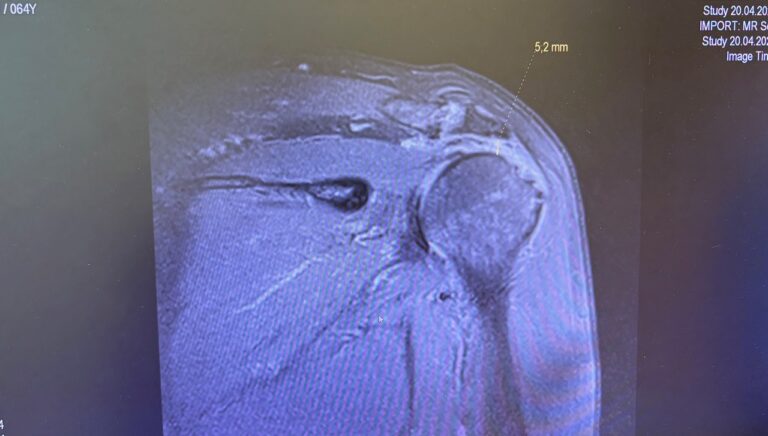

Ο ώμος συμμετέχει σε όλες τις κινήσεις του χεριού και ως εκ τούτου εκτίθεται σε έντονες καταπονήσεις. Οι συχνές επαναλαμβανόμενες υπερφορτώσεις οδηγούν σε παθήσεις που οφείλονται στη φθορά, π.χ. βλάβη στο στροφικό πέταλο ή αρθρίτιδα της άρθρωσης του ώμου. Τα ατυχήματα και οι αθλητικές κακώσεις μπορούν να προκαλέσουν τραυματισμούς στους τένοντες και τους συνδέσμους. Η τυποποιημένη διάγνωση και θεραπεία του πόνου στον ώμο έχει σημειώσει σημαντική πρόοδο τα τελευταία χρόνια. Συμπτώματα που φαινομενικά μοιάζουν μεταξύ τους μπορεί στην πραγματικότητα να έχουν πολύ διαφορετικές αιτίες.

Δεδομένου ότι οι επαγγελματικές και αθλητικές απαιτήσεις των ασθενών αυξάνονται και οι ηλικιωμένοι γίνονται όλο και πιο δραστήριοι, πρέπει να αναγνωρίζονται και να αντιμετωπίζονται οι αιτίες και οι παράγοντες που προκαλούν τα προβλήματα στον ώμο. Η διάγνωση βασίζεται στο ιστορικό, σε κλινική εξέταση και σε περαιτέρω διαγνωστικές απεικονιστικές εξετάσεις. Ο στόχος της θεραπείας μας δεν είναι μόνο η εξάλειψη του πόνου, αλλά και η καλή λειτουργία του ώμου.

- Ρήξη στροφικού πετάλου

- Σύνδρομο υπακρωμιακής προστριβής